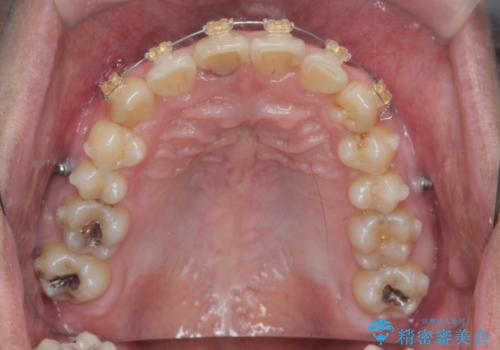

2級ディープバイト 遠心移動を伴うマウスピース矯正

・深い噛み合わせ(ディープバイト) ・2級性の咬合関係(上顎前突)・前歯のがたつき

以上のような歯並びの問題をマウスピース矯正インビザライン・カリエール・マイクロインプラント・部分ワイヤー矯正

を用いて改善していきます。

深い噛み合わせと上顎前突の状態を治すのに時間がかかりましたが、治療後は理想的で安定した咬合関係となりました。